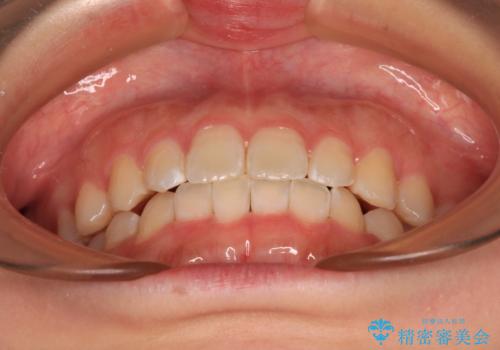

前歯のデコボコを整える インビザラインによる矯正治療

毎日の装着時間をしっかりと守っていただいたことで、1年程度で無事に治療を終えることができました。